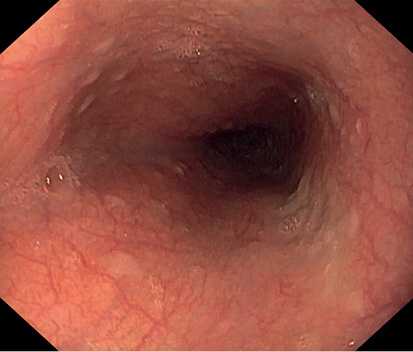

По данным ЭГДС, выполненной при поступлении: на фоне недостаточности кардии и неэрозивного рефлюкс-эзофагита на уровне 33 см от резцов по заднеправой стенке пищевода расположено экзофитное новообразование полиповидной формы размером 8×5 мм белесой окраски, выступающее в просвет на 4—5 мм, симптом шатра отрицательный (рис. 1, 2). Поверхность новообразования гладкая, сосудистый рисунок прослеживается.

Рис. 1. Новообразование по заднеправой стенке пищевода. Фото авторов.

Рис. 2. Новообразование по заднеправой стенке пищевода. Фото авторов.